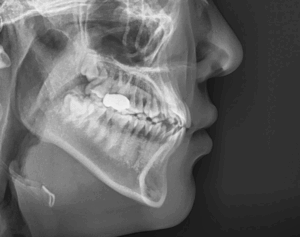

절단 및 개방 교합, 주걱턱 고민, 수술 없이 비발치 치아 교정으로 해결한 케이스

안녕하세요, 교정과 전문의 김정은입니다. ​ 오늘 소개해 드릴 내용은 흔히 주걱턱이라 불리는 골격성 3급 부정교합에 대한 내용을 소개해 드리려 합니다. ​ “턱이 좀 나와 보인다”​는 얘기를 들어본 적 있으신가요? ​…